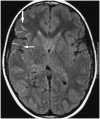

Swirl Sign

On noncontrast CT, image of the active bleeding into an epidural hematoma is identified as the swirl sign (Fig. 26) (49,50). The active component of uncoagulated blood is of lower attenuation than the surrounding clotted blood, forming an area of low attenuation in an otherwise hyperattenuating hematoma (50). The recognition of this sign identifies actively bleeding epidural hematomas, resulting in the appropriate intervention for the patient (50).

caption a8Swirl sign.